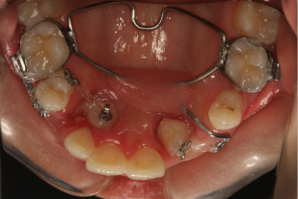

【精彩病例】